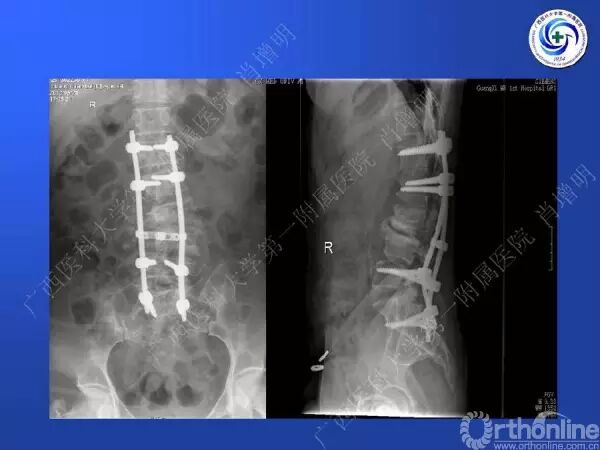

退变性脊柱侧凸是由于椎间盘退变后继发小关节退变,椎管和神经根管容积变化以及脊柱失稳,畸形等病理改变,以疼痛和神经压迫症状为主要表现的常见疾病。

退变性脊柱侧凸多发于50岁以上的中老年群体,是现代常见的老年疾病。多年来,针对该病的临床研究一直没有停步,广西医科大学第一附属医院肖增明教授细致地介绍了该病的诊疗进展。